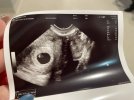

• IMG_7598.jpeg

IMG_7598.jpeg

2,2 MB · Wyświetleń: 124